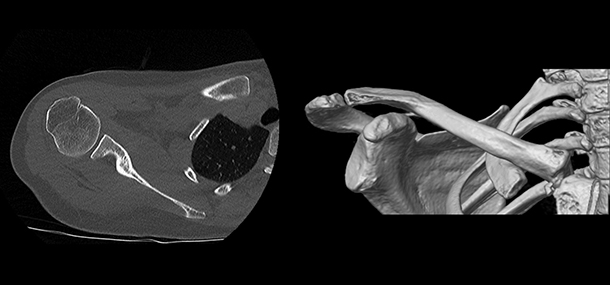

The cross-sectional images produced during a CT scan can be reformatted in multiple planes and even create three-dimensional images. These images can be viewed on a computer monitor, printed on film, or transferred to a CD or DVD.

CT images of internal organs, bones, soft tissue, and blood vessels provide more detailed information than conventional soft beam X-rays, particularly for soft tissues and blood vessels.

- Unlike conventional X-rays, CT provides very detailed images of many types of tissues, including the lungs, bones, and blood vessels.